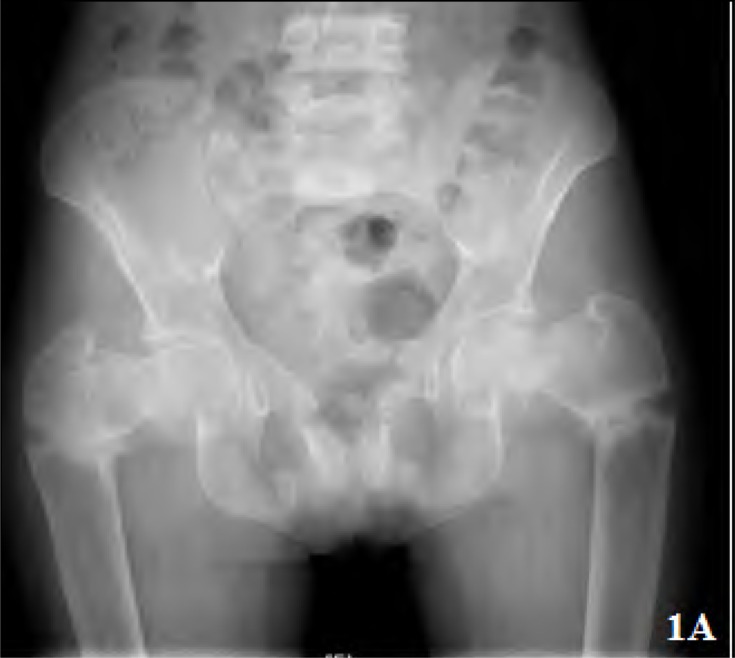

Results: Of the 380 patients with clinically suspected pSS, 25 had RTA. The median age was 32 (18-60) years. Nineteen patients had complete RTA. Six had incomplete RTA. Only 10 patients (40%) had symptoms related to RTA at presentation. Sixteen patients (64%) had present or past history of hypokalemic paralysis. Pseudofractures were seen in 7 patients and an additional 2 had subclinical radiological osteomalacia. Majority of the patients (61.2%) had a normal 25(OH) D3 level. Those with osteomalacia had significantly lower serum phosphate, blood ph and higher alkaline phosphatase. Serum calcium and 25(OH) D3 levels were not significantly different between patients with osteomalacia and those without.